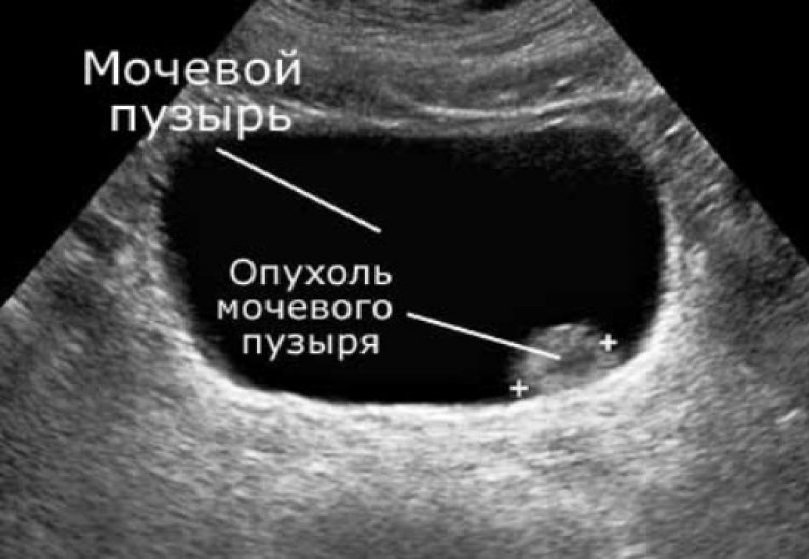

Следует пройти трансабдоминальное УЗИ мочевого пузыря, которое может выявить опухоли размером больше 0,5 см, локализованные в областях боковых пузырных стенок. Проводят исследования МРТ для исследования мочевого пузыря и органов малого таза. Для обнаружения рака, который расположен в зоне шейки, применяют трансректальное сканирование. Иногда используют трануретальную эндолюминальную эхографию.

Обязательными исследованиями при онкологии мочевого пузыря считается метод цистоскопии (для уточнения размеров, местоположения и внешнего вида опухоли) и биопсия.